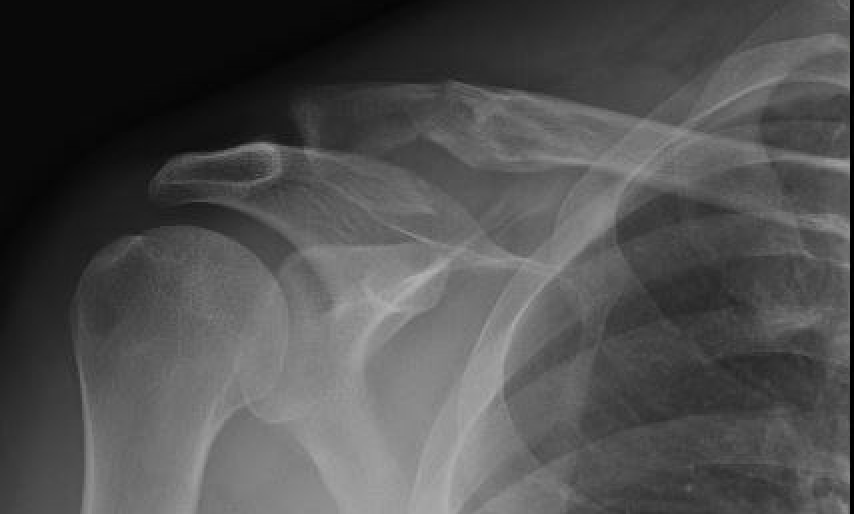

Neer Classification

Fracture lateral to the CC ligaments Non displaced

|

Fracture medial to the CC ligaments CCL ligaments attached to lateral fragment Medial fragment displaced superiorly |

Between conoid and trapezoid Conoid disrupted Trapezoid remains attached to the lateral fragment |

Lateral to CC ligaments Intra-articular extension Stable |

Periosteal sleeve disruption Pediatric Medial fragment displaced |

Comminuted Type II Medial fragment displaced |

Type I

Type II

Type V

Nonunion

Robinson and Cairns JBJS Am 2004

- cohort of 100 displaced Type II fractures treated nonoperatively

- 11 had symptomatic nonunion

- 21 had asymptomatic nonunion

- reasonable outcome scores with nonunion

- recommended non operative treatment in middle aged / elderly